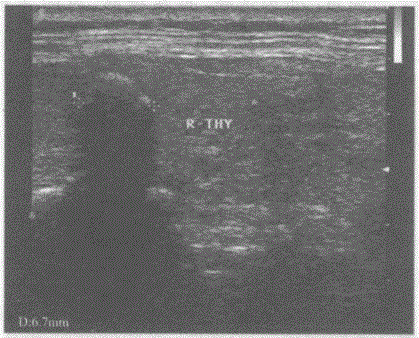

问题 临床资料:女,37岁,常规体检。 超声综合描述:甲状腺右叶可见直径0.7cm弧形强回声光带,后伴声影。 超声提示:

选项 A.慢性淋巴细胞性甲状腺炎(桥本氏病) B.甲状腺结石(右叶) C.甲状腺异物(右叶) D.甲状腺钙化灶(右叶)

答案 D